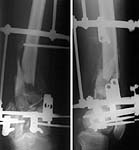

We decided to manage the case with closed ex-fix at the moment, with maybe autografting in case of bone loss. I perfomed some kind of "wireless Ilizarov" with separate fixation of both condyles. I am not too happy with current xrays and plan to perform gradual correction. It seems to me that condyles are overreduced to flexion. The device looks stable enough so tibial extension IMHO is not needed. When i give up with correction i'll insert olive wires into condyles and remove half-pins. See attachment for X-rays and view of the device.